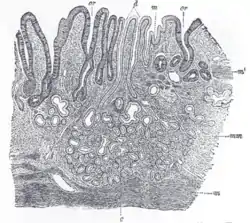

Section of the human esophagus. Moderately magnified. Section of mucous membrane of human stomach, near the cardiac orifice.

Section of mucous membrane of human stomach, near the cardiac orifice. Section of mucous membrane of human rectum. X 60.